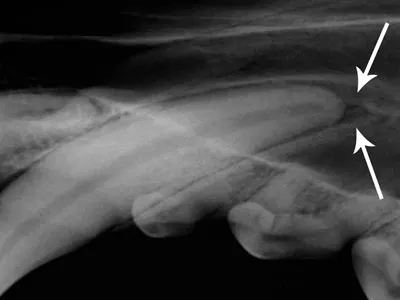

However, radiographs often reveal a small, regular widening of the periodontal space at the apex of the maxillary canines (Figure 1). This common artifact is known as a chevron effect, summation effect, or penumbra. Although this may appear to be a periapical lesion, it is differentiated from a pathologic abnormality because it is regular and v-shaped, as opposed to irregular and round (Figure 2).

Figure 1: The small, regular, v-shaped widening of the periodontal space at the apex of this maxillary canine is an artifact known as the chevron effect (arrows).